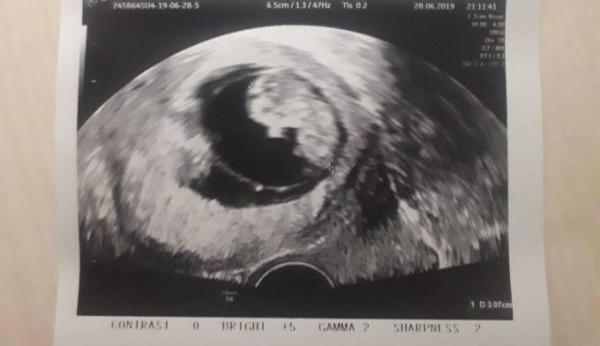

Guten Abend ihr Lieben, Ich hatte ja seither eine relativ angenehme Frühschwangerschaft. Ausser der Kreislaufprobleme, dem Bluthochdruck und der Stimmungsschwankungen hatte ich ja nie wirklich was. Jetzt hätte ich heute etwas Blut am Klopapier, was mir nach meinem Abgang letztes Jahr im März ziemlich Sorgen gemacht hat, also mein Freund mich ins Auto gepackt und ins Krankenhaus gefahren und was soll ich sagen... Sorgen warum total unberechtigt, Krümel geht es einwandfrei. Hat kräftig mit den Füßchen gestrampelt und am Daumen genuckelt. Als mein Freund gucken gekommen ist, hat der Wurm sogar kurz gewunken, das war so schön anzusehen! Die Blutung war vermutlich nur ein geplatztes Äderchen. Heute kann ich beruhigt schlafen

Bild zu Ausflug ins Krankenhaus - Forum für Januar - Mamis

Ein schönes Bildchen. Zum Glück ist alles gut